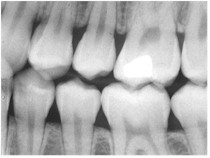

A dental x-ray requires holding a piece

of film behind the teeth

Medical and dental x-ray technicians

often wear a badge that contains photographic film to

monitor how much stray x-ray radiation they receive in

their jobs. The film in the badge is checked

periodically to see how much exposure was received.